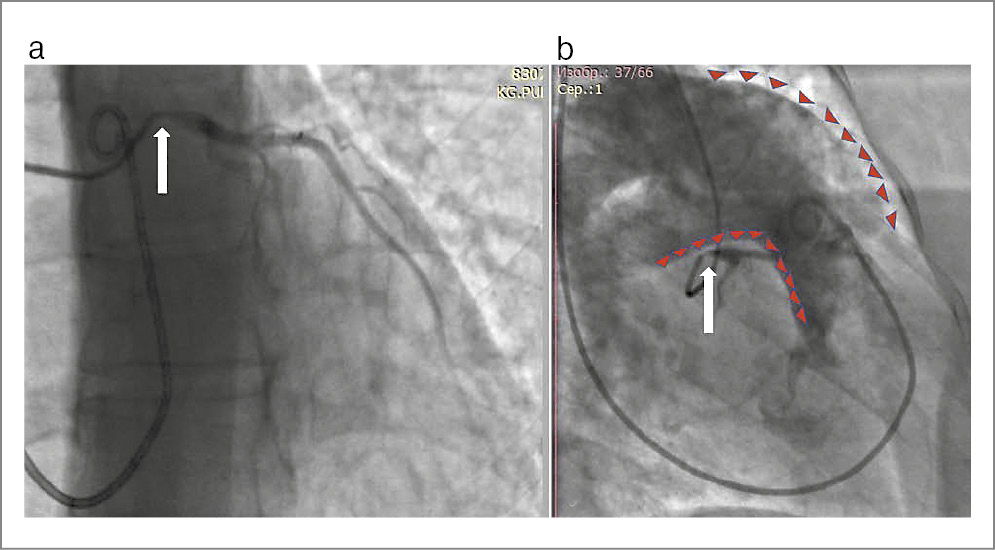

По данным катетеризации правых отделов сердца давление в ЛА 81/35/50 мм рт. ст., давление заклинивания ЛА 9 мм рт. ст., сердечный выброс 3,9 л/мин, ЛСС 841 дин/см/с-5. По данным контрольной коронарографии от 24.03.2022 стентированный сегмент ствола ЛКА без признаков рестеноза (рис. 3).

Рис. 3. Контрольная коронарография. Стентированный сегмент ствола ЛКА указан белой стрелкой.